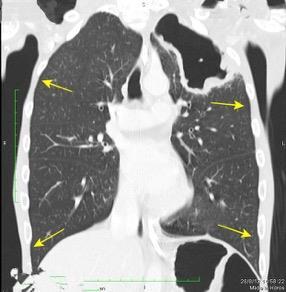

Derrame pleural..33,3% Derrame bilateral.26,7% Ganglios mediastínicos e hiliares..66,7%..

No hiliares

Okada F et al. Chest HRCT findings in acute transformation of adult T-cell lymphoma/leukemia. Eur Radiol 2015

Vidrio deslustrado 60%. Consolidación 33,3% Nódulos…33,3%